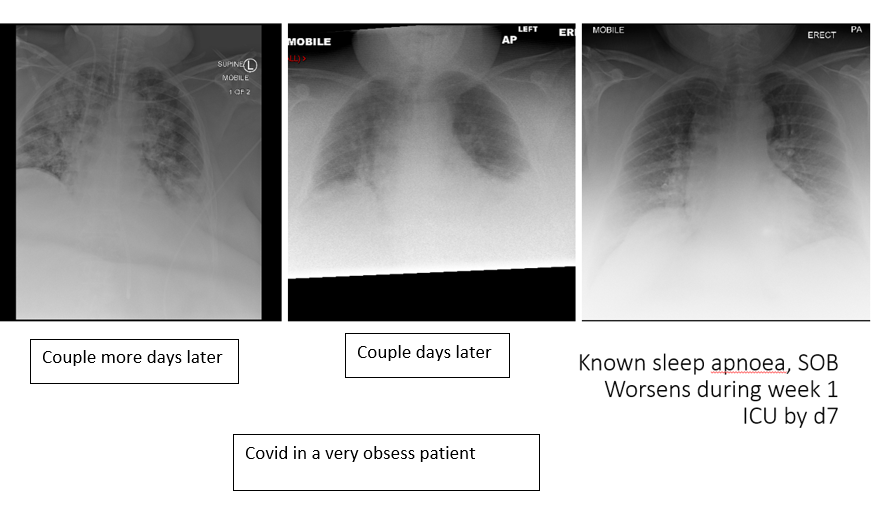

COVID-19 is predominantly a respiratory illness

CXR is a critical diagnostic/prognostic marker in COVID19, and provides the most cost-effective biomarker

3 things a CXR is sensitive to that can be related to covid:

1) Pneumonia

2) Heart failure

3) Early ARDS (acute respiratory distress syndrome

This makes a normal CXR reassuring (when compared with ECG) that major complications are not present

~80% will have mild (40%) to moderate (40%) disease, most will recover

Moderate disease will include a mild form of pneumonia on a CXR

Bilateral infiltrates and ground glass opacity are the most commonly reported signs on CXR and CT imaging

Bilateral interstitial pneumonia is a serious infection that can inflame and scar your lungs

Ground-glass opacity (GGO) is a finding seen on chest x-ray (radiograph) or computed tomography (CT) imaging of the lungs.

It is typically defined as an area of hazy opacification (x-ray) or increased attenuation (CT) due to air displacement by fluid, airway collapse, fibrosis, or a neoplastic process